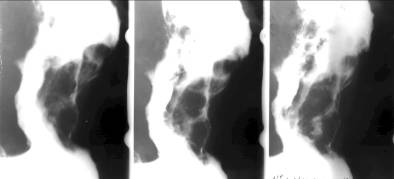

Carcinoamele vegetante se dezvolta ca mase tumorale în interiorul lumenului gastric.

Expresia radiologica a acestui tip de tumora este lacuna care are un contur neregulat, cu imagini de semiton. Jonctiunea cu peretele normal este distincta si formeaza un unghi ascutit. Leziunea poate fi mica, dar poate ajunge la dimensiuni mari putând cuprinde 1/3 -2/3 din stomac. Pliurile mucoasei gastrice sunt întrerupte la nivelul leziunii, iar peretele este rigid. Tumora se poate localiza oriunde la nivelul stomacului, dar de cele mai multe ori prefera regiunea antrala.

Carcinomul infiltrativ

În aceasta forma, procesul începe în submucoasa si musculara, mucoasa ramânând un timp îndelungat intacta.

Initial, procesul este limitat la o zona mica a peretelui. Aceasta zona este rigida, nu participa la peristaltica, undele ajung la extremitatea ei proximala si se continua la extremitatea distala. Ea poate prezenta miscari de basculare, fiind asemanata cu miscarea unei scânduri pe valuri.

Când procesul cuprinde circular peretele gastric, lumenul se stenozeaza stomacul devenind bilocular

În forme mai avansate, infiltratia poate cuprinde o regiune gastrica mai extinsa cum ar fi regiunea antrului piloric sau a fornixului. În acest caz, observam o îngustare a regiunii interesate, rigiditatea peretelui gastric, absenta undelor peristaltice. Trecerea spre regiunea sanatoasa se face gradual.